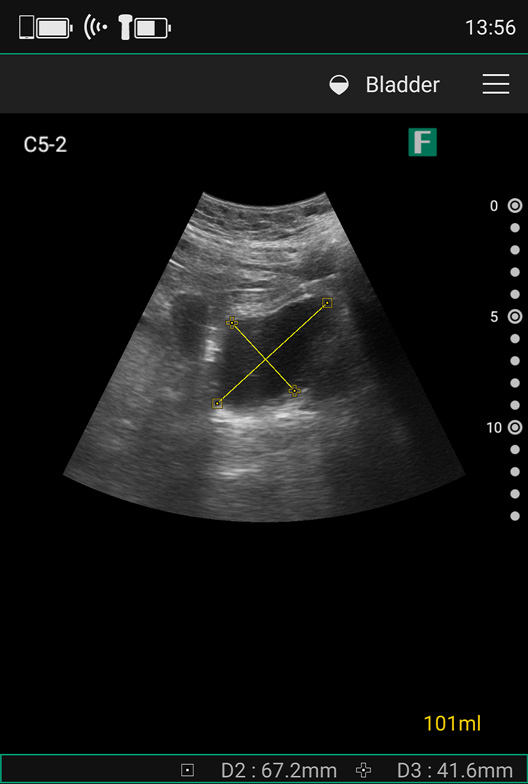

当院では前立腺IMRTの前処置として1時間前に排便・排ガス、排尿をしてもらい、それから1時間の畜尿を行い、照射直前に撮影する位置合わせ用のCone-beam CT(CBCT)画像で尿量を確認していますが、CBCT画像で確認した尿量が少ない場合は、再度蓄尿した後に改めてCBCTを撮影しなければならず、それには大きな手間と患者さんの被ばくが伴います。そこで、当院ではポータブルエコーiViz airを用いて、CBCTの撮影前に尿量を把握することで、患者さんおよび診療放射線技師の負担軽減、放射線治療のスループット向上につなげています。

当院の放射線治療領域において、これまでエコーが使用される場面はまったくなく、私自身も実際の患者さんに使用した経験はありませんでしたが、iViz airの膀胱尿量自動計測は、膀胱を描出するだけで、尿量を自動計測してくれるので、すぐになじめ、尿量測定に関しては十分に使いこなせるようになれたと感じています。また、私の他の診療放射線技師3名もこれまでエコーを使用した経験がなかったのですが、すぐに使いこなせるようになりました。

さらに、前立腺IMRTの患者のうち研究に同意した5名161回分を対象として、その診療放射線技師がiViz airで測定した尿量と、私がCBCT画像から測定した尿量を比較した研究において、iViz airとCBCTの尿量の測定結果には強い相関(r2 = 0.9607)が認められ、尿量が正確に測定できていると感じています。

現在は、患者さんに治療室に入ってもらい、ベッドに寝てもらってからiViz airで尿量を測定します。そこで尿量が足りなければ待合室で飲水してしばらく待機してもらい、尿量に問題がなければCBCT撮影から照射へと進めています。

尿量については、治療計画時の量と毎回正確に一致させることまでは求められず、患者さんごとに許容値を決め、許容値範囲の中で日々判断しながら治療を実施していきます。その中で、これまでは判断に迷う場面もありましたが、膀胱尿量自動計測機能は尿量が数値で出るため、CBCT画像を目視だけで確認していた時よりも自信を持って判断ができるようになったと思います。

また、尿量測定時、数値だけでなく画像が見られる点も重要で、ポータブルエコーを用いることで一人ひとりの患者さんの膀胱の位置をしっかりと確認できるので、尿量が少ない場合でも正確に測定することができます。